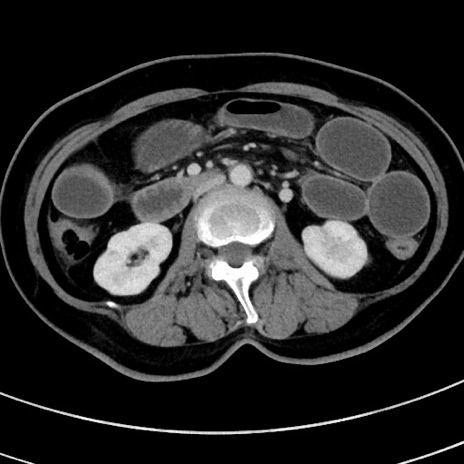

症例9(横断像)

【症例】 60歳代女性

【主訴】むかつき、みぞおちの痛み

【現病歴】3日前よりむかつきがあり、食事がとれない。

【既往歴】糖尿病

【身体所見】発熱なし、心窩部圧痛軽度あるも、腹膜刺激症状なし。

【データ】WBC 7400、CRP 1.92